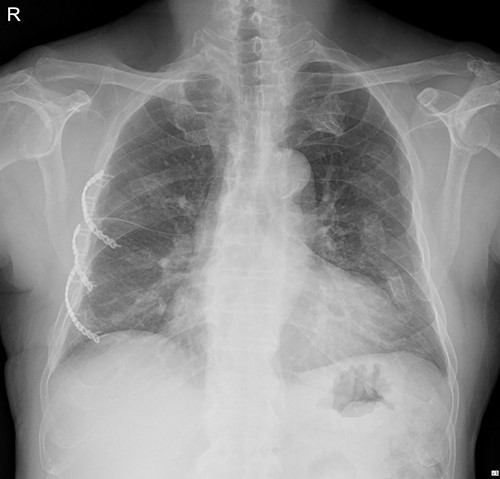

On 25 November 2021, a 68-year-old male, a victim of a motor vehicle accident, presented with multiple rib fractures and hemopneumothorax in the right hemithorax. On hospital Day 2, oxygen saturation gradually dropped under 90% despite proper support, and the patient’s right chest wall showed a newly occurred flail motion. We decided to stabilize rib fractures emergently. The operation was performed routinely, with bicortical screw fixation after exploration of the thoracic cavity. There were no specific intraoperative or postoperative events, and the patient was safely discharged from the hospital with stitches removed on hospital Day 17 (Fig. 1.).